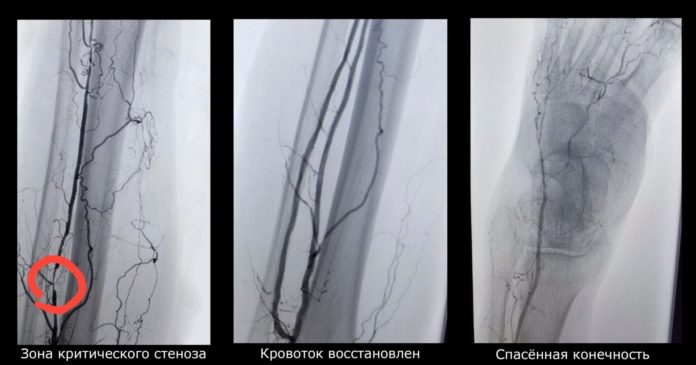

Пациенту провели контрастное исследование сосудов (ангиография), оно точно показало локализацию и степень сужения артерий. Сразу после диагностики был выполнен малоинвазивный сосудистый доступ.

Через небольшой прокол в артерию под контролем рентгена был введен специальный тончайший проводник. Он прошел через заблокированный участок сосуда. Затем по нему доставили баллон, который в нужном месте раздулся, расширил просвет артерии и восстановил кровоток. Это метод баллонной ангиопластики.

В результате операции кровоток в конечности был восстановлен, а мучительные боли были купированы уже в первые сутки. У пациента появился шанс на заживление язвы. Конечность была спасена от ампутации.